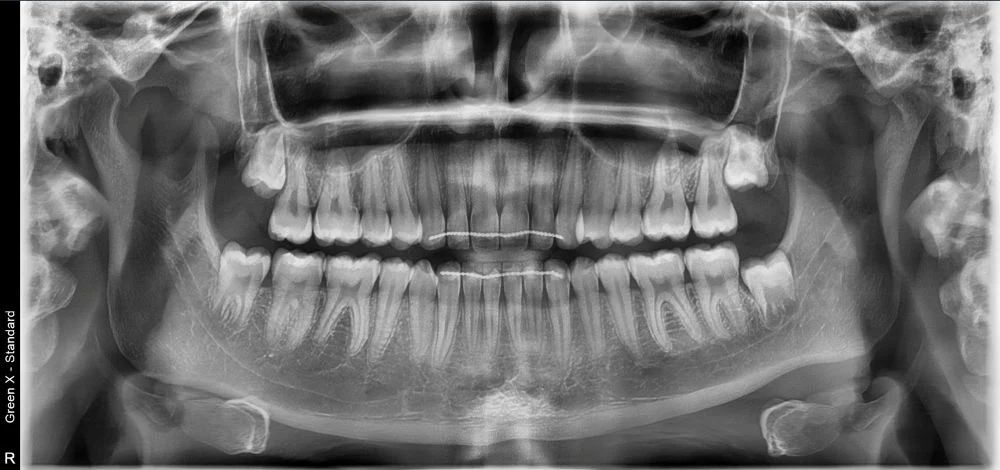

- wyraźne obrazy 2D i 3D — pomocne przy implantach, ósemkach, leczeniu kanałowym i ortodoncji

Pantomogram pokazuje cały stan uzębienia i kości — dzięki temu można wykryć zmiany, których nie widać na małym zdjęciu punktowym (jak torbiele, stany zapalne czy problemy ze stawami). To proste badanie, które warto wykonać profilaktycznie co kilka lat.

Tomografia CBCT tworzy trójwymiarowy obraz zębów, kości, zatok i stawów.

Pozwala na precyzyjne planowanie:

- implantów,

- usuwania ósemek,

- leczenia kanałowego,

- aparatów ortodontycznych,

- diagnostyki bólu zatok i stawu skroniowo-żuchwowego.